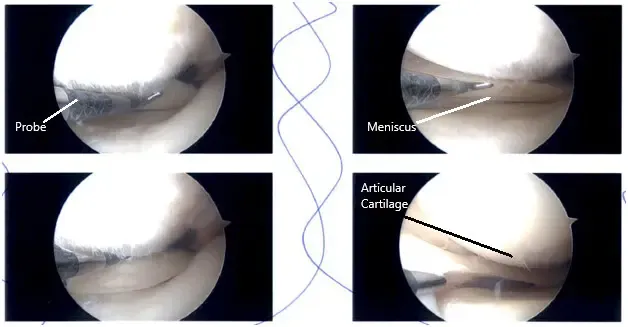

Imágenes de artroscopia intraoperatoria.

Había una ruptura en el margen libre interno en el menisco medial y lateral. Se identificó un ablandamiento en la superficie inferior del cuerno posterior del menisco medial sin lesión abierta.

El LCA estaba intacto en la muesca intercondilar. El cartílago del cóndilo femoral medial y lateral permaneció intacto. Hubo cambios de grado 1 a 2 en la troclea y cambios de grado 3 a grado 4 en la faceta rotuliana inferior medial. El margen interno del menisco medial y lateral estaba equilibrado a través de un margen estable.